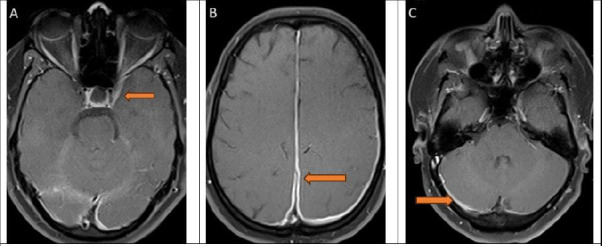

Hypertrophic pachymeningitis (HP) is characterised by thickening of the cranial or spinal dura mater, and it encompasses idiopathic and secondary forms. Later is linked to infections, inflammatory conditions, and autoimmune disorders. This rare condition presents with a myriad of neurological manifestations, including headaches, cranial nerve palsies, and visual disturbances. A South-Asian woman in her mid-thirties presented with a three-month history of left-sided headache, double vision, and facial numbness. Neuroimaging revealed diffuse thickening of the dura mater, suggestive of hypertrophic pachymeningitis (HP). Diagnostic workup excluded infectious and autoimmune causes, categorising the condition as idiopathic. Treatment with corticosteroids led to significant improvement in her symptoms. HP is a rare cause of headache in young patients, and diagnosis relies on neuroimaging and CSF analysis, necessitating the exclusion of secondary causes through comprehensive evaluation. Treatment varies based on the underlying aetiology. Corticosteroids remain the first-line drug for idiopathic cases.